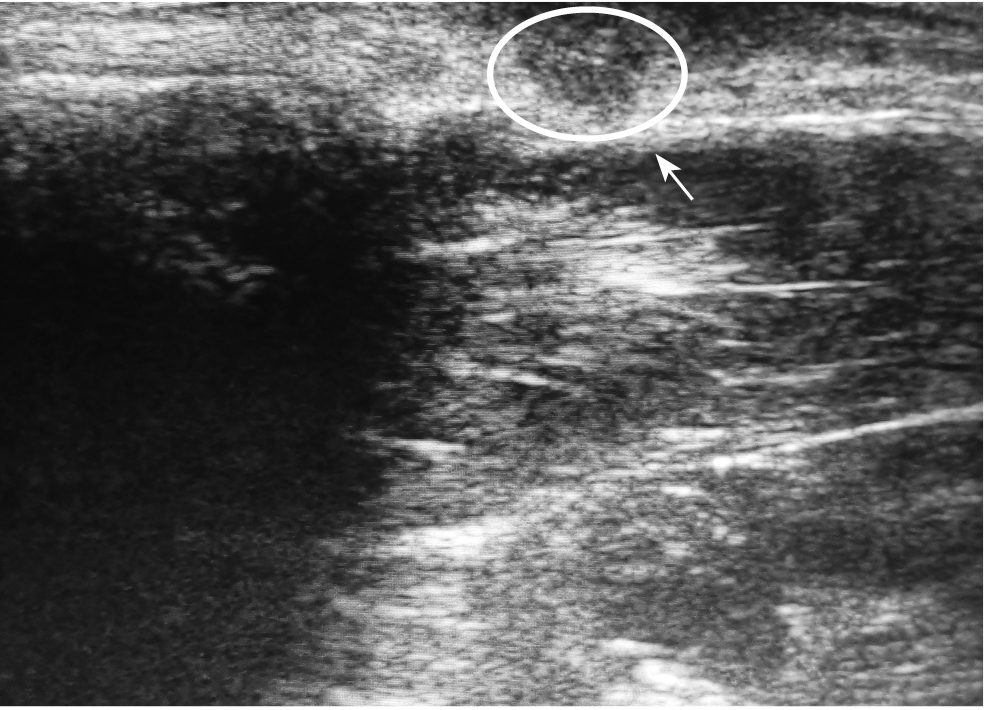

The ultrasound technique followed the rules developed by us for the examination of mass lesions: scans were performed in two compulsory views (transverse and longitudinal, relative to the axis of the finger phalanx) and arbitrary (relative to the axis of the mass) [3]. At ultrasonography, the MCs looked like an additional single-chamber mass of round or oval shape with clear even contours. The MC wall had the appearance of an echogenic line. In 14 (22.5%) patients with recurrences the MCs were two-chambered. The MC structure was visualized as homogeneous anechogenic (i.e. fluid), in 42 (67,7%) cases MC had echogenic inclusions after treatment attempts by crushing or puncture. Examination of the nail phalanx in all patients allowed to determine an uneven and indistinct line of periosteum with prominence in the form of osteophyte and deformation of the articular gap of the distal interphalangeal joint, proximal interphalangeal joint, interphalangeal joint of the thumb (signs of osteoarthritis). In all cases, the MC pedicle derived from the cavity of the corresponding interphalangeal joint in the area of osteophyte location (Fig. 5).

Fig. 5. Mucous cyst of the III finger, recurrence after the surgery. Ultrasonography: the circled area shows a cavity of a mucous cyst with a pedicle from the distal interphalangeal joint